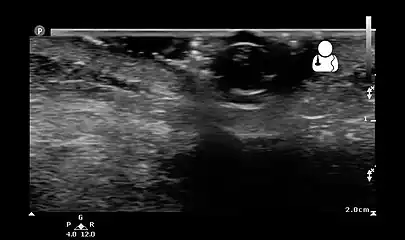

- Ultrasound showing maggot infestation[22]

Ultrasound showing maggot infestation[22]